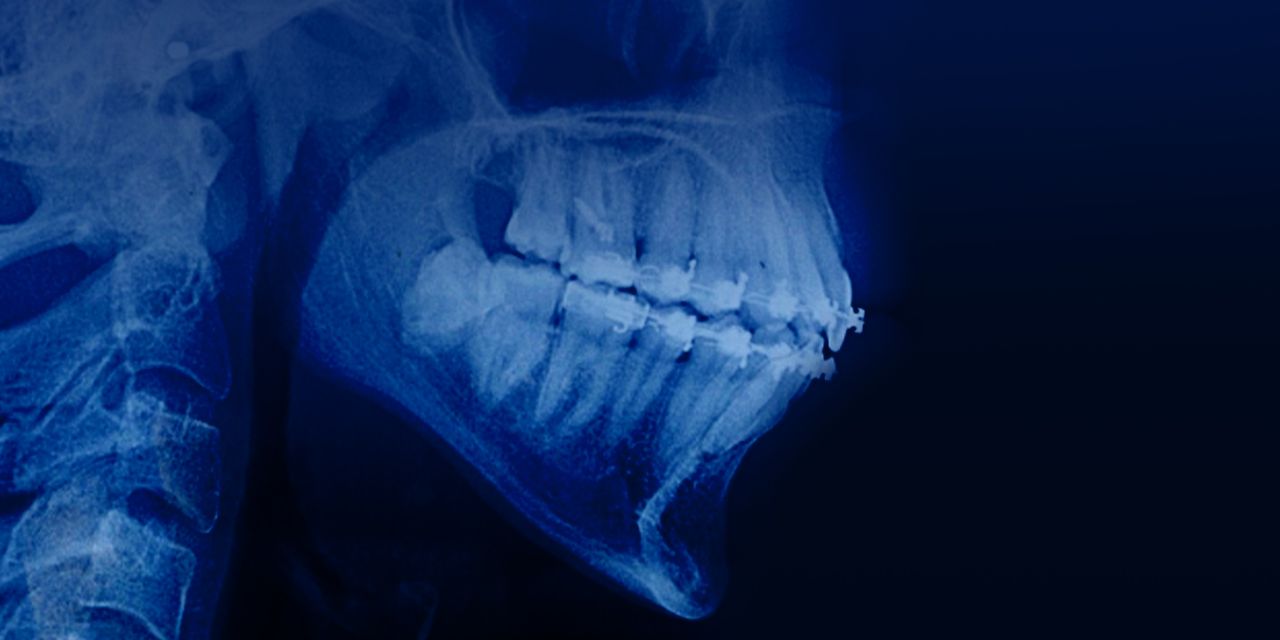

Tratamiento de pacientes adultos con mordidas profundas: enfoque basado en la evidencia

– Características de la maloclusión de la división 2 de la clase II

– ¿Por qué la mordida profunda ocurre en este tipo de maloclusión?

– ¿Cómo decidir entre la intrusión de incisivos superiores/inferiores y/o la rotación de la mandíbula hacia abajo y hacia atrás?

– ¿Cómo incluir el ángulo del plano mandibular en el proceso de toma de decisiones?

– ¿Cuándo utilizar la mecánica efectiva del arco de intrusión para la verdadera intrusión?

– ¿Cuándo utilizar cables de curva inversa para la intrusión relativa?